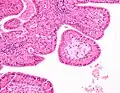

| Cytopathology of Warthin's tumor, with typical cellular features (and a relatively uncommon binucleated cell).[1] Pap stain. | |

The appearance of this tumor under the microscope is unique. There are cystic spaces surrounded by two uniform rows of oncocytes, which are epithelial cells with abundant, granular, eosinophilic cytoplasm.[7] The cystic spaces have epithelium referred to as papillary infoldings that protrude into them. Additionally, the epithelium has lymphoid stroma with germinal center formation.